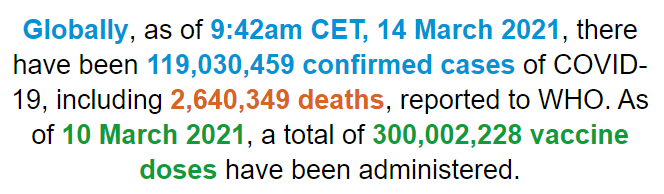

陶金医生立即根据患者主诉完善各项检查,结果发现患者心电图未见异常、心衰标志物也正常、体征与心脏病也不符。但听诊时发现右侧呼吸音低,与气胸表现很相似,便询问浦阿姨最近有没有其他不适。随后,家属的回答却让陶医生大吃一惊。原来,浦阿姨年后总感觉腰腿疼,医院MRI检查显示腰椎间盘突出。正巧女儿的朋友开了一家按摩针灸所,于是针灸店的老板就上门为阿姨行针灸治疗。3月4日下午一点多钟,当针灸师在浦阿姨腿上针灸15分钟后,又在她右上背施针。 图片由院方提供

图片由院方提供“当时虽然隔着厚厚的棉衣,但突然感到一阵刺痛,一直沿袭到大腿。因为不适感只是一瞬间,也就没太在意”,浦阿姨回忆,可之后的两三个小时,越发觉得不对劲,当时就感觉胸闷、气喘不上来。